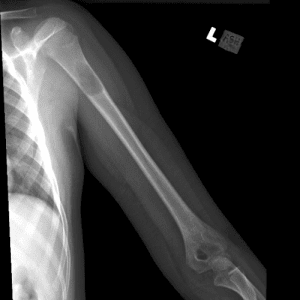

Pediatric Radiographs